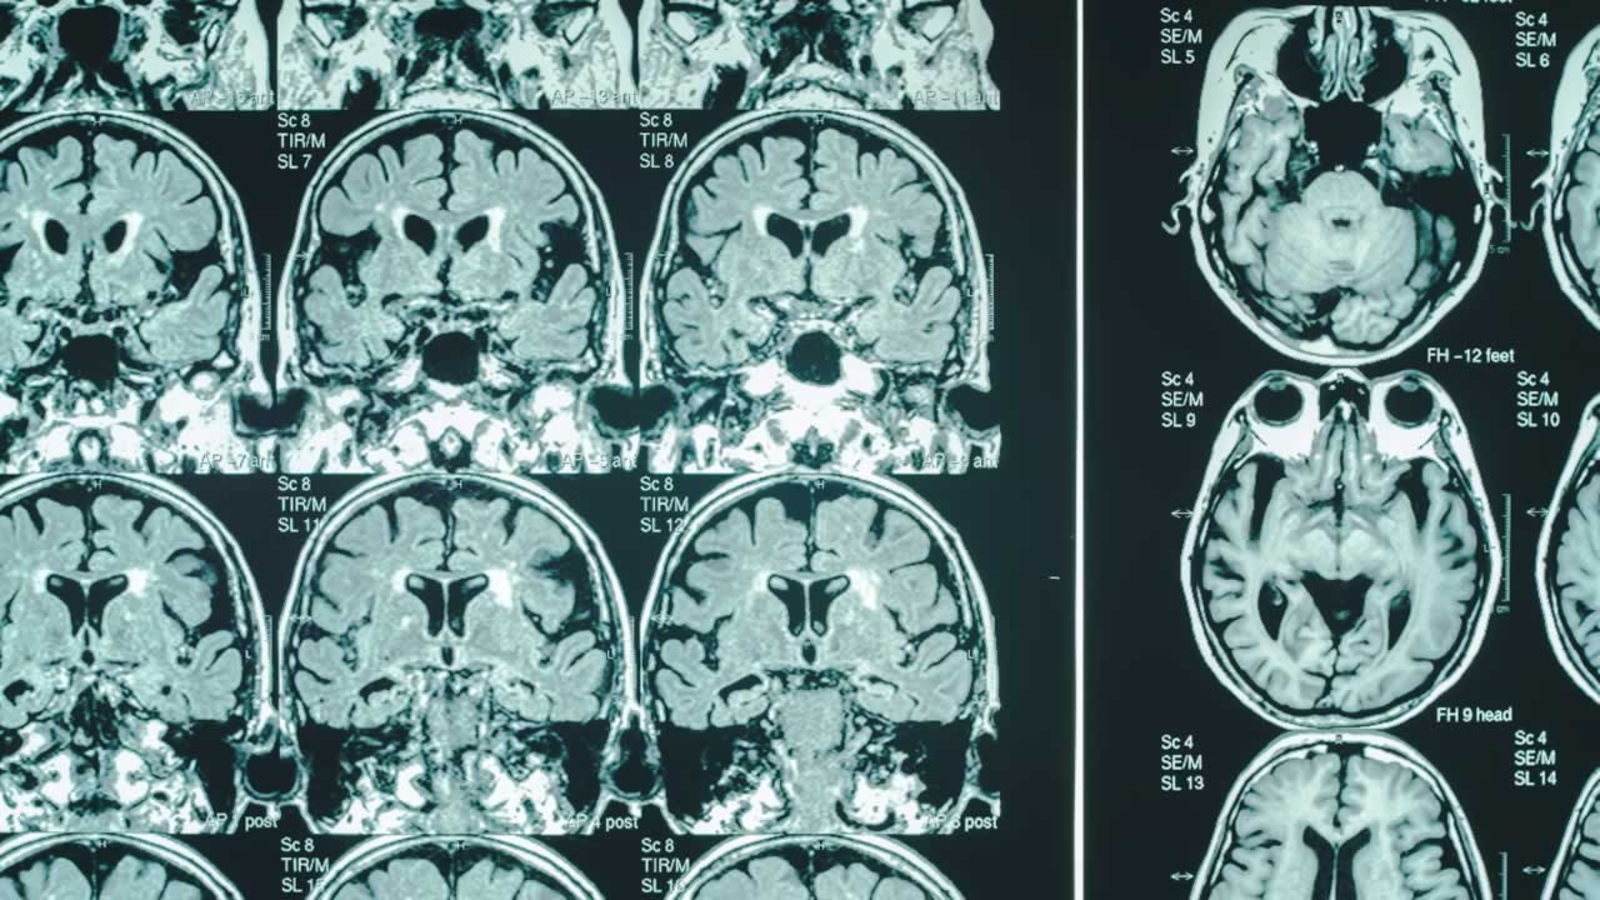

SAN FRANCISCO (KGO) -- A new report out this week reveals an increase in both costs and prevalence of Alzheimer's disease.